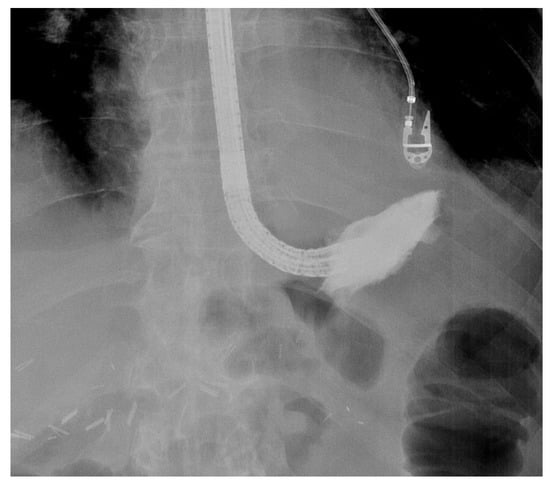

4. Endoscopic Vacuum Therapy Procedure

5.2. Intra-Procedure Difficulties